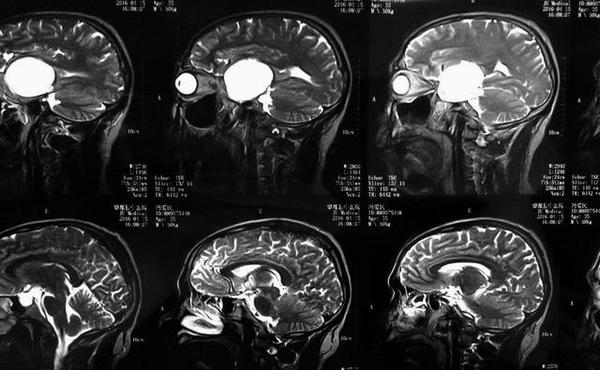

MRI表现:病灶中相对脑实质来说T WI上呈等信号,或稍低信号,信号均匀,少数内部见小片高信号。T WI及T 一FLAIR上均为明显高信号。CSHAs的血供丰富及解剖结构较复杂,术前误诊率和术后致残率均较高,掌握其CT、MR及DSA等各种影像学检查方面的特征性表现,可提高术前定位及定性诊断的准确率,对于临床治疗方案的制定、确定手术入路以及减少手术致残及致死率有着十分重要的意义。

有学者认为海绵窦海绵状血管瘤与雌激素、孕激素和促性腺激素的水平有关 。而Ohata等则认为这是颅内高血流状态和动脉收缩压升高所致。有文献报道部分患者有腺垂体功能减退的症状,与肿瘤向鞍内生长有关。海绵窦海绵状血管瘤的影像学特点为同时累及鞍旁和鞍内的单发大肿块,呈哑铃状,密度多均匀而少出血和钙化,其在CT扫描时呈等或稍高密度,瘤内常无钙化,可侵蚀颅骨,但一般不伴骨质增生。MRI扫描时T wI明显高信号和显著均质强化是其重要的诊断依据 ” 。